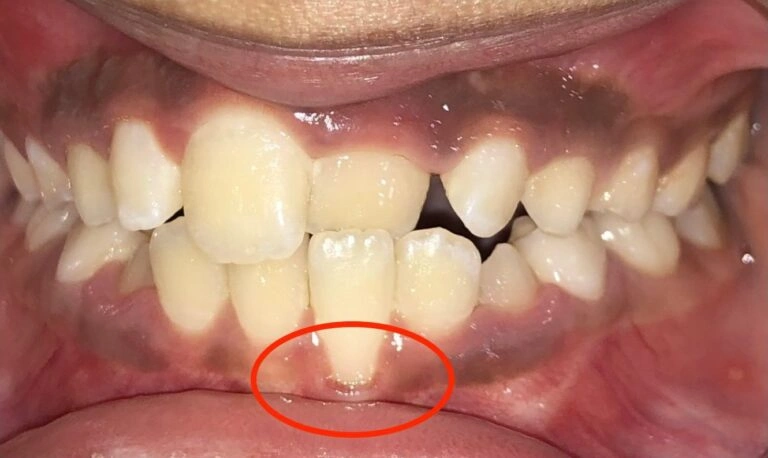

3. Localized Gum Recession: When the Gums Aren’t Protecting the Teeth

The third issue parents need to be aware of is localized recession. This occurs when the gums and bone no longer cover the teeth properly, exposing the roots.

While this might seem like a minor concern, it can actually lead to sensitivity, pain, and even tooth loss.

Visual Example:

Patient Example (young child)